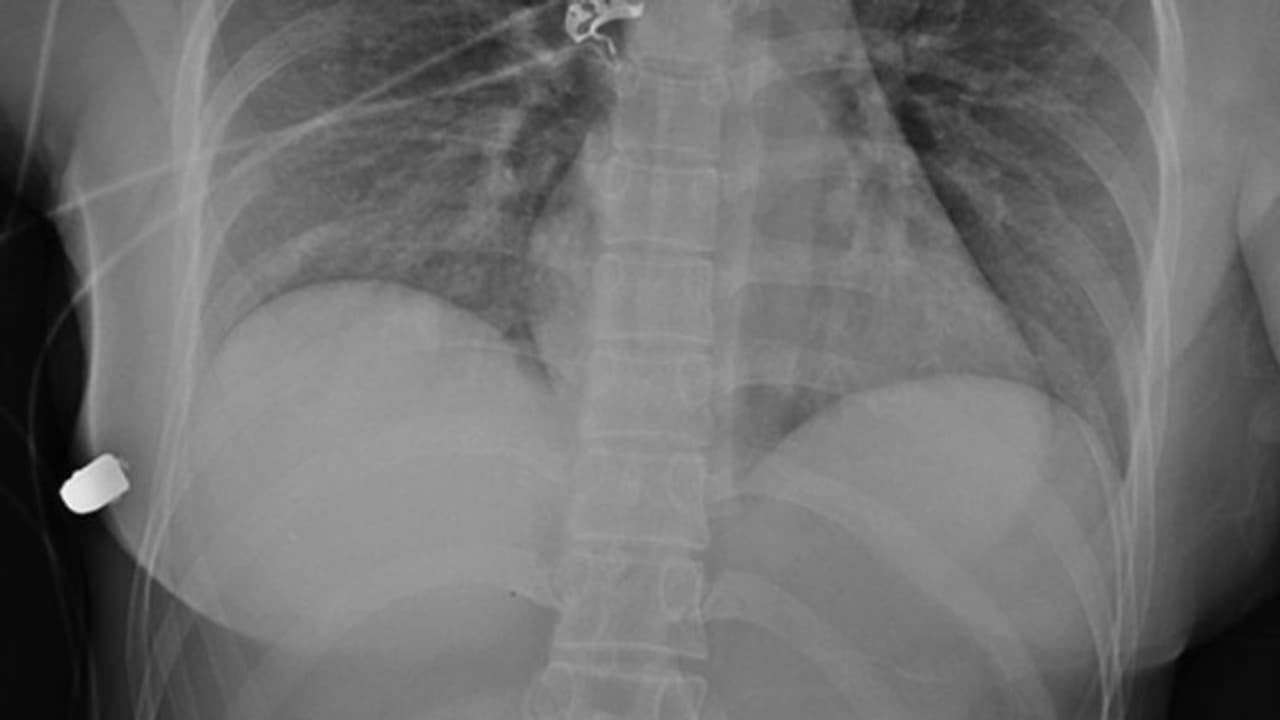

റോഡിലൂടെ നടന്നുപോകവേയാണ് യുവതിക്ക് അജ്ഞാതന്റെ വെടിയേറ്റത്. ഉടന് തന്നെ ഇവരെ ആശുപത്രിയില് പ്രവേശിപ്പിച്ചിരുന്നു. തുടര്ന്ന് വലത്തേ സ്തനത്തില് നിന്ന് ഡോക്ടര്മാര് വെടിയുണ്ട കണ്ടെടുക്കുകയും ചെയ്തു. അത്ര അകലെ നിന്നല്ലാതെ വന്ന വെടിയുണ്ട ഇടത്തേ സ്തനം തുളച്ച് അകത്തുകയറി, സിലിക്കണ് ജെല്ലില് തട്ടിത്തെറിച്ച് വലത്തേ സ്തനത്തിലെത്തിയെന്നാണ് ഡോക്ടര്മാര് വിശദീകരിച്ചത്.

വാരിയെല്ലുകള്ക്ക് പരിക്ക് പറ്റിയെങ്കിലും ഹൃദയം, ശ്വാസകോശം തുടങ്ങിയ സുപ്രധാനമായ ആന്തരീകാവയവങ്ങള്ക്ക് യാതൊരു കേടുപാടും സംഭവിച്ചില്ല. അത്യപൂര്വ്വമായ സംഭവമെന്ന നിലയ്ക്ക് ഈ സംഭവം പഠനവിധേയമാക്കുകയായിരുന്നു വിദഗ്ധര്. യുവതിയുടെ സ്കാനിംഗ് റിപ്പോര്ട്ടും മുറിവുകളുടെ ഫോട്ടോഗ്രാഫുമെല്ലാം പുറത്തുവന്നിട്ടുണ്ട്.